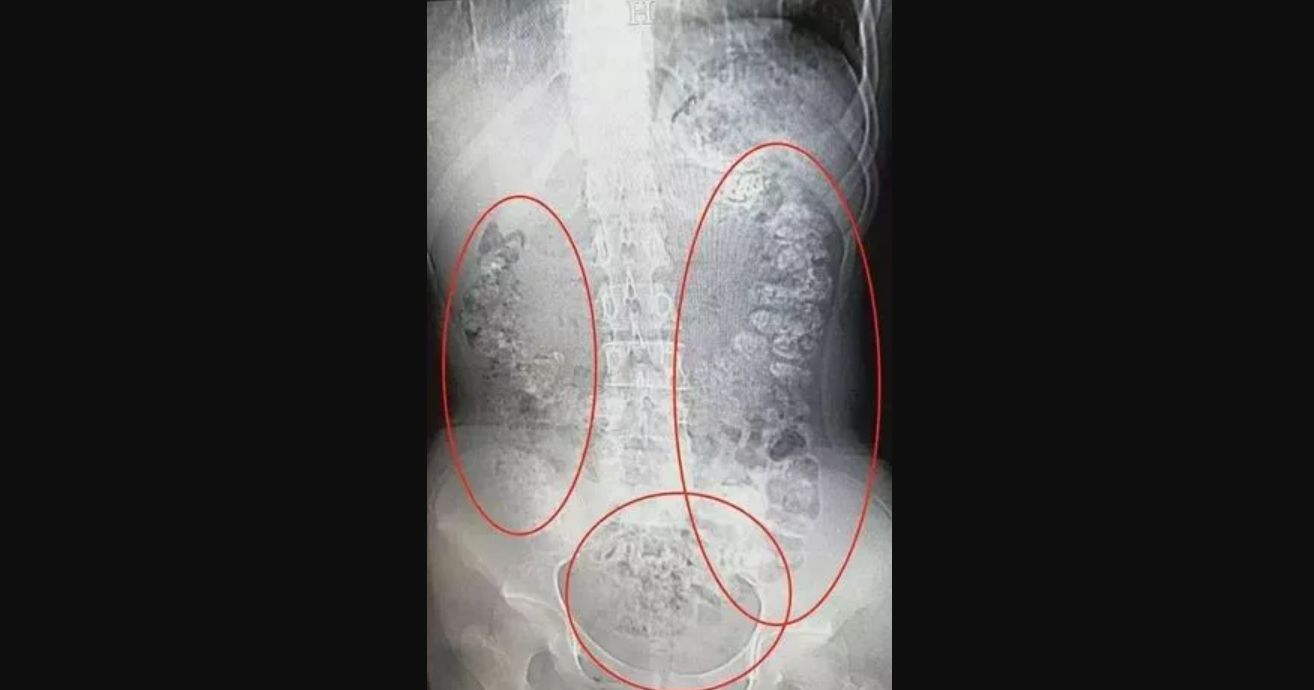

O tym, jak niebezpieczna może być bubble tea przekonała się 14-latka z Chin, która po wypiciu modnego napoju trafiła do szpitala. Dziewczyna skarżyła się przez kilka dni na zaparcia i bóle brzucha.

Badania wykazały mnóstwo ziarnistych cieni w żołądku i jelitach. Okazało się, że to niestrawione kulki z bubble tea, które tkwiły w przewodzie pokarmowym pacjentki i zaburzyły jego pracę. Była ich ponad setka.

Na szczęście, wszystko skończyło się dobrze, wystarczyły podane przez lekarzy środki przeczyszczające.